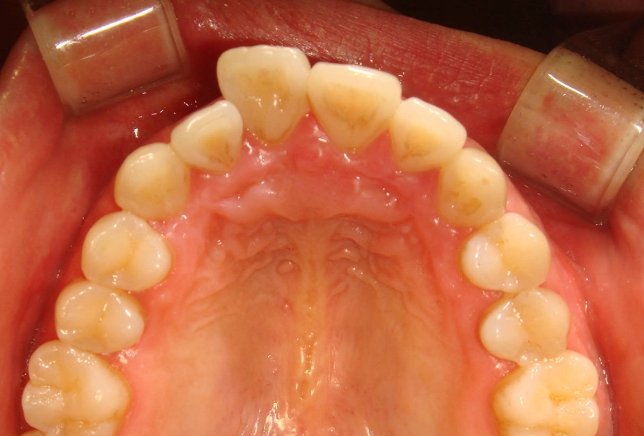

신논현역 치과 스마일 뷰에서 진행하는 설측 부분교정은 교정이 필요한 치아 안쪽에만

장치를 붙여서 치아를 이동하는 방법이에요.

치아 전체에 장치를 붙여서 치아를 이동하는 것보다는 훨씬 수월하고 시간도 짧고

치아 몇 개에만 장치가 들어가니 비용도 그만큼 적겠지요?

특히 신논현역 치과 스마일 뷰에서 많은 분들이 진행하는 설측 부분교정은

일부러 말하지 않으면 주변 사람들이 전혀 인식하지 못할 만큼 감쪽같이 진행할 수 있답니다.